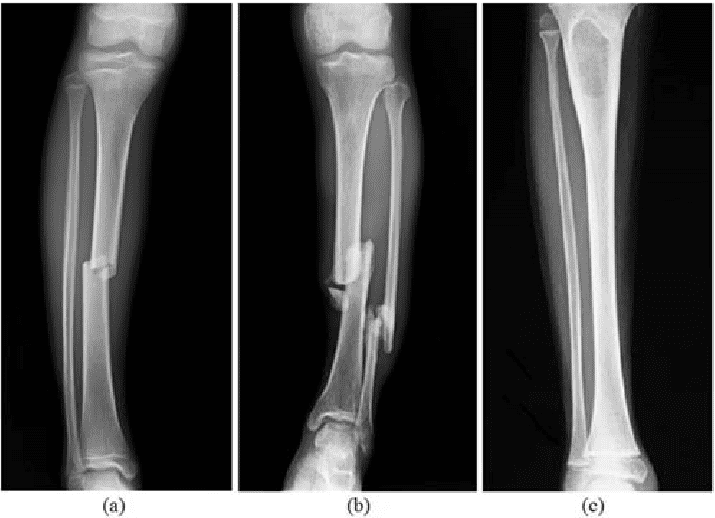

Bir röntgen çıktısı ekleyerek sonuçlara bakalım..

Fotoğrafımızı yükledik ve görüntüyü inceleyerek teşhis koymasını talep ettik. Aldığımız sonuç son derece şaşırtıcı ve büyüleyici oldu.

Yüklediğimiz fotoğrafın ne olduğunu tespit etti. Bu bir röntgen fakat yapay zeka belli algoritmaları aşamadığı taktirde siyah-beyaz bir fotoğraf. Baktığımız zaman bu durum yapay zeka için eski fotoğraf makinesi ile çekilmiş nostaljik bir kareyi anımsatabilir. Fotoğraf karesi üzerinde doğru tespit yapmakla kalmadı. Bununla birlikte kırık yerlerin analizini çıkartarak teşhiste koydu.